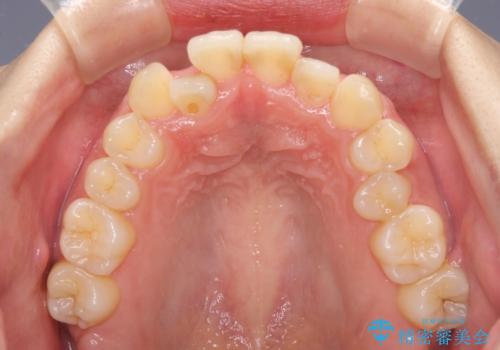

- 前歯のデコボコを気にして来院された患者様です。

上顎右側犬歯が八重歯になっており、それによって奥歯が前方に移動しているため、右側の咬み合わせの改善が必要と判断されました。